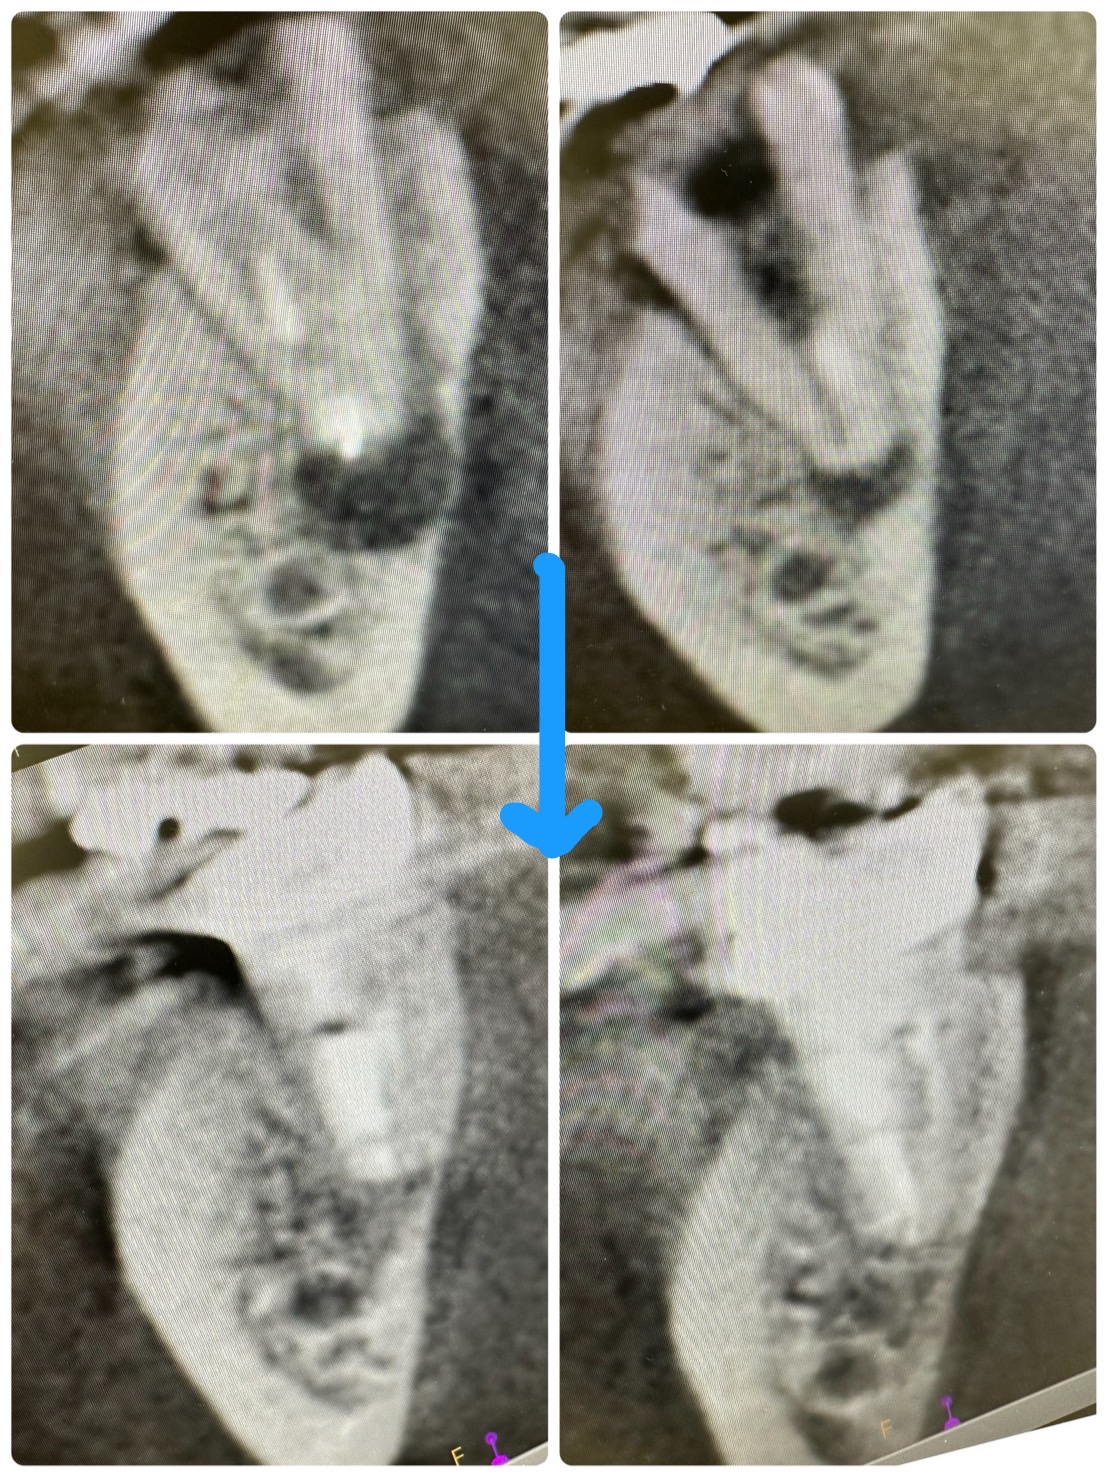

次は病巣

根充後1年経過、非常に良く治っている

ヤグレーザーにMTA根充が良い‼️